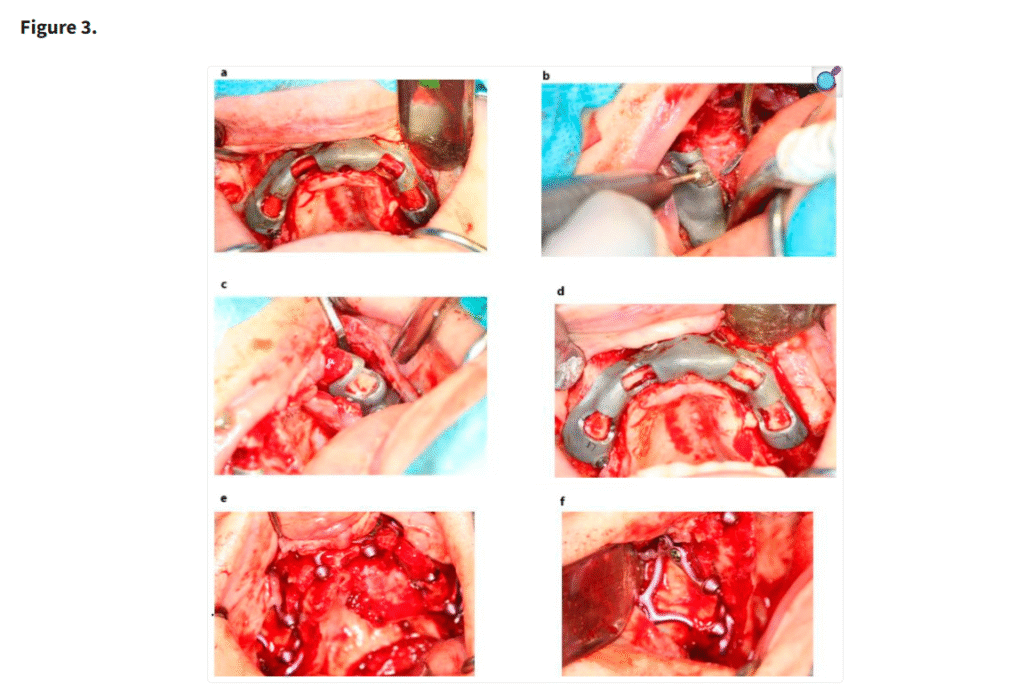

テンプレートの臨床応用(a–d)と、骨整形後の MaI インプラント®(Integra Implants®, ロッツ〔ポーランド〕)の埋入(e, f)